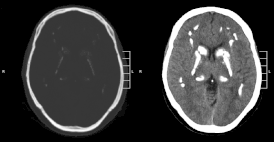

Идиопатическая кальцификация базальных ганглиев 1 (Синдром Фара) характеризуется накоплением кальция в различных областях мозга, преимущественно в базальных ганглиях. Деградация функций нервной системы у пациентов с синдромом становится заметной в возрасте от 30 до 50 лет, но может появиться в детстве или в более позднем возрасте.

Симптомы заболевания — деградация двигательных функций, деменция, судороги, головная боль, утомляемость, дизартрия, мышечная спастичность, атетоз. Также могут отмечаться симптомы паркинсонизма — тремор, ригидность мышц, маскоподобное лицо, шаркающая походка, «катающие» движения пальцев; такие симптомы обычно развиваются на поздних стадиях. Чаще наиболее заметна дистония и хорея. Также может развиваться психоз, в том числе напоминающий шизофрению.